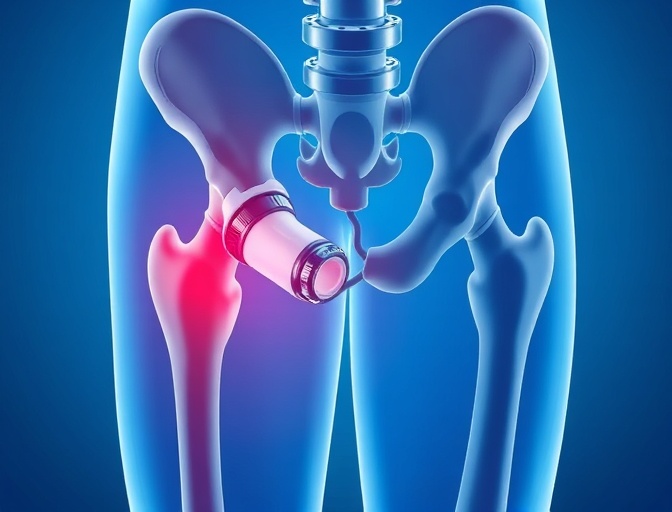

Hip Replacement

Comprehensive hip replacement solutions using anterior approach techniques that promote faster recovery and reduced pain.

Robotic-Assisted Surgery

Our Mako Robotic-Arm Assisted Surgery system enables unparalleled precision in joint replacement procedures, resulting in better implant positioning and improved outcomes.